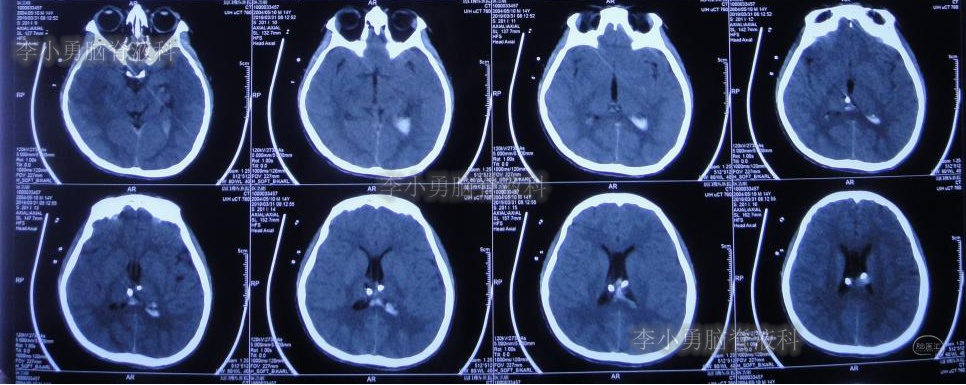

2019年3月26日患者突发头痛及呕吐,随后出现晕厥。急救车送至河南省周口市某医院。行头颅CT(图-1):脑室内出血,次日急诊给予行双侧脑室外引流术(图-2)(第一次的脑室外引流术)。

图-1:2019年3月26日头颅CT:脑室内出血

图-2:2019年3月27日头颅CT:双侧脑室外引流术后

双侧脑室外引流5天后即2019年3月31日,脑脊液颜色由血性明显变淡,意识转清,肢体活动良好,给予复查头颅CT(图-3):脑室不大,残留少许积血。

图-3:2019年3月31日头颅CT:残留少许积血